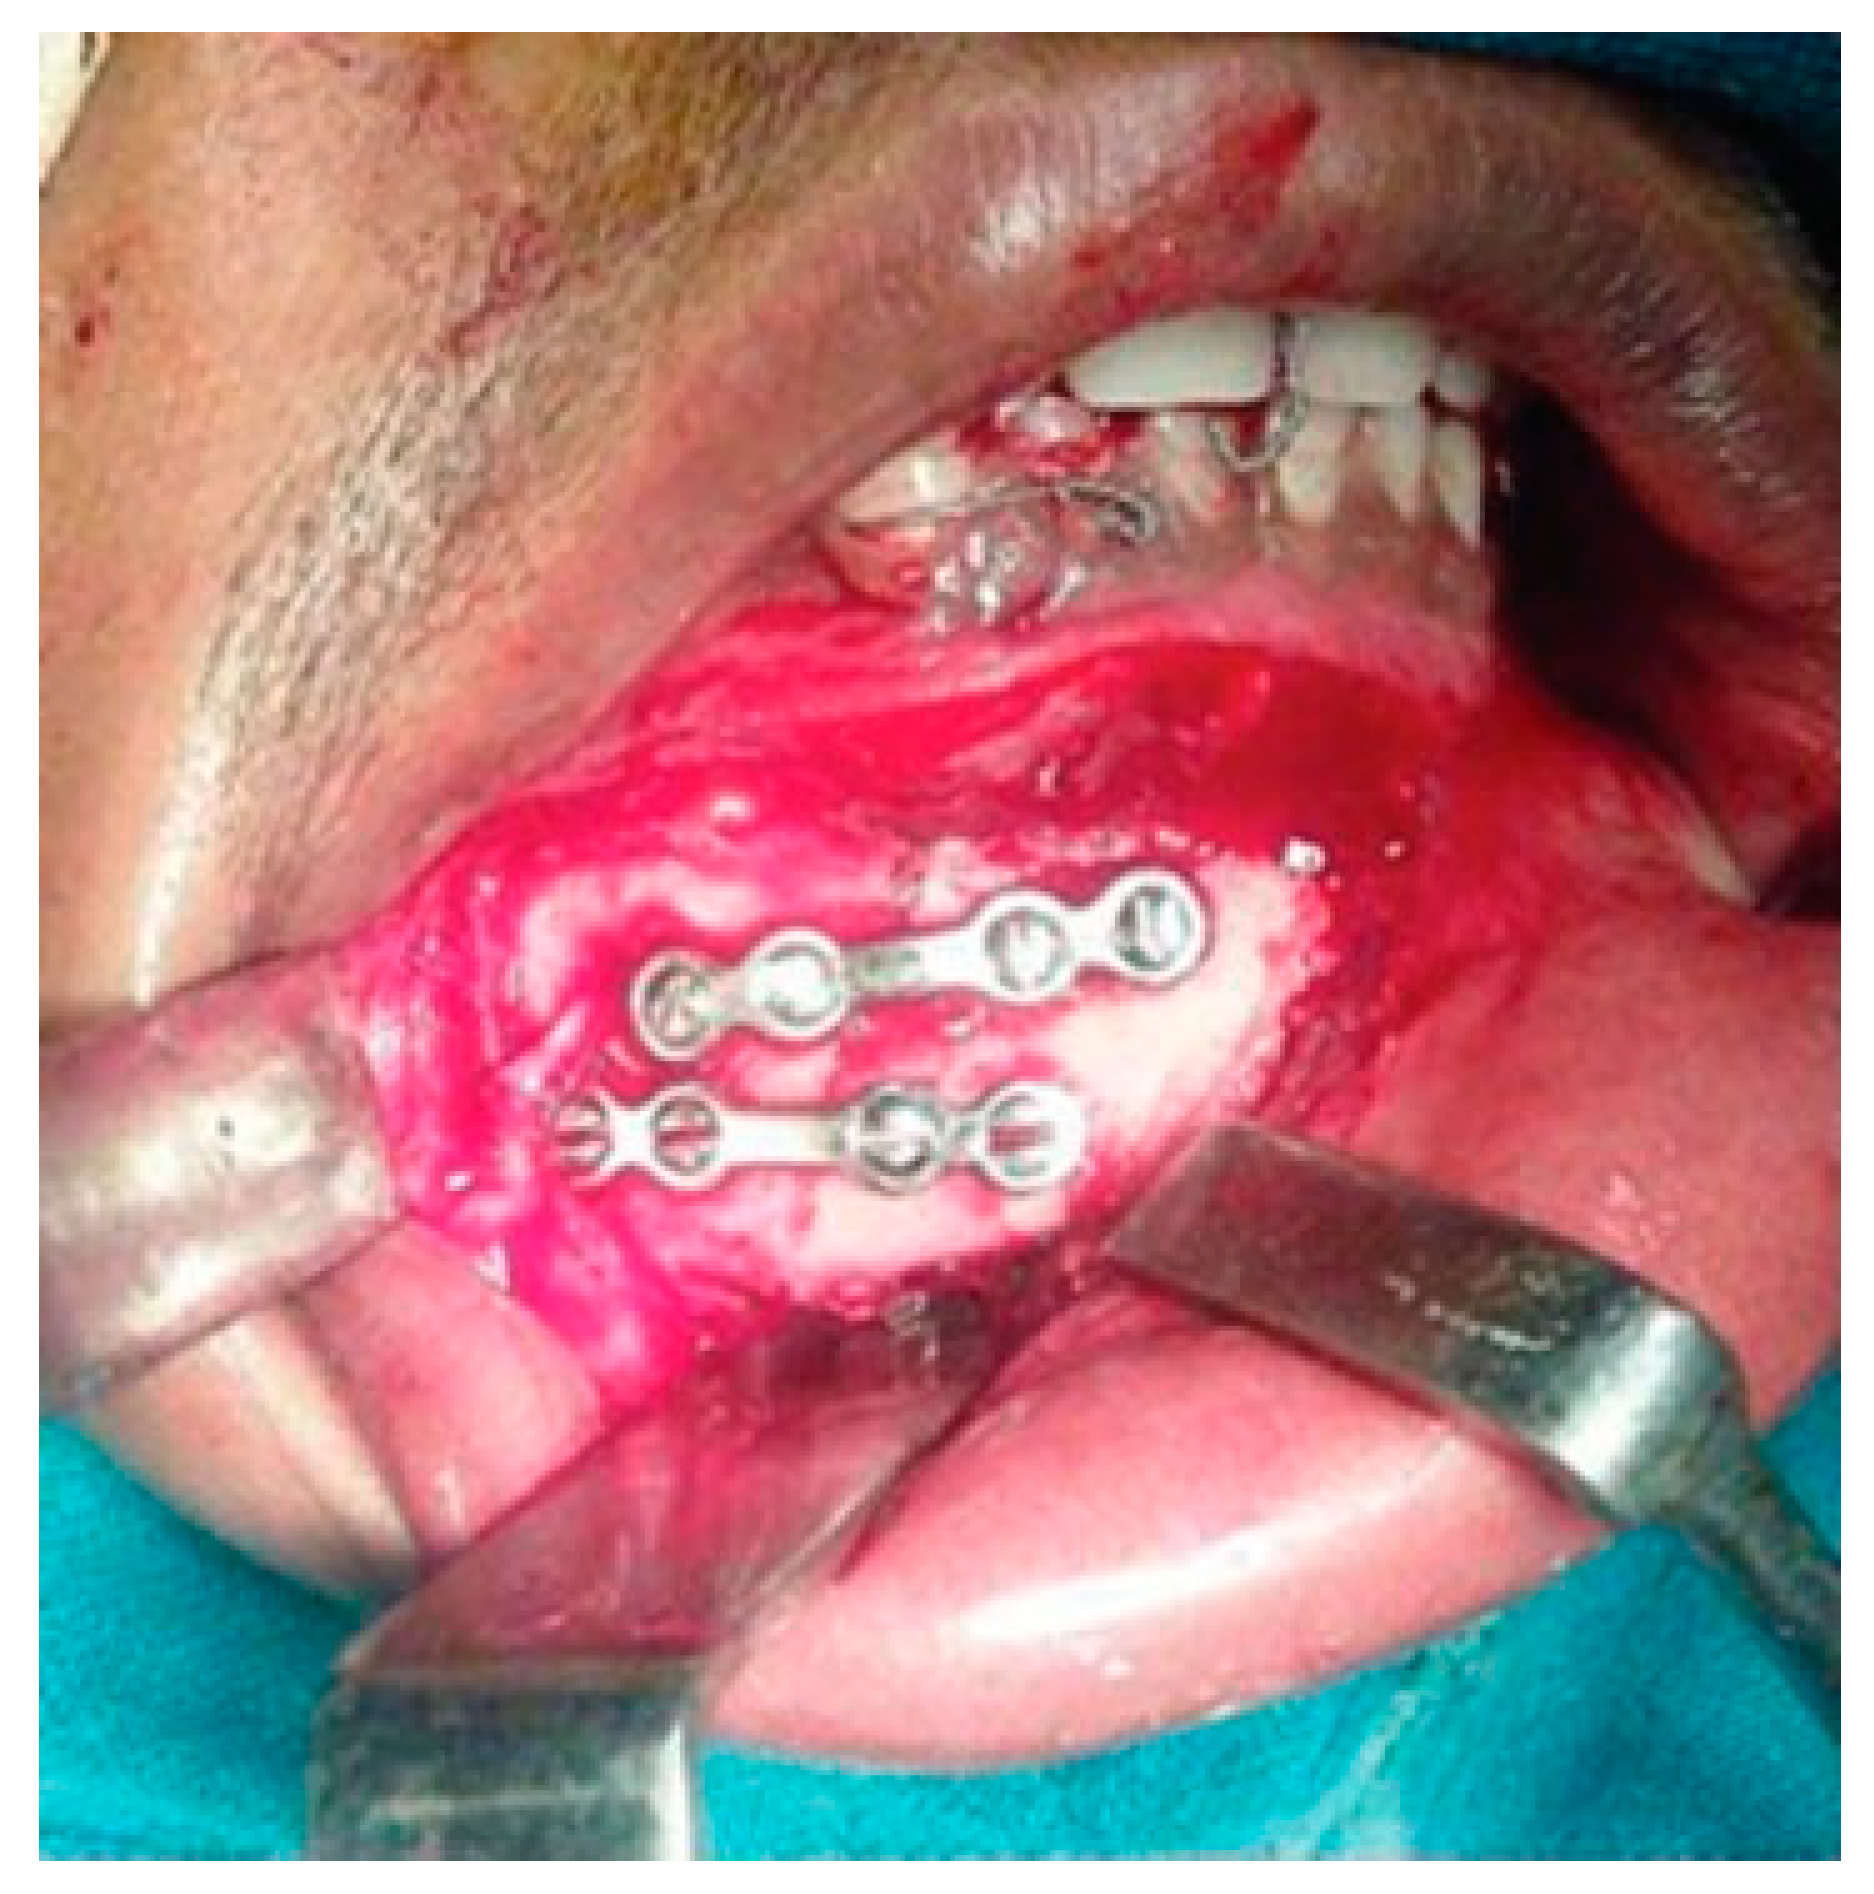

For the illustration of the technique, a case of left angle fracture with right parasymphysis fracture of the mandible has been depicted (Figure 1). With the mouth open, stainless steel wires (24 gauge) approximately 15 cm were introduced through the facial embrasure between the maxillary molars, premolars, and the maxillary central incisors. Next, the palatal end of the wire is looped and then passed through the opposing lingual embrasure in the mandible (Figure 2).

Next, the fracture sites were exposed and segments were reduced appropriately, and then all the embrasure wires were twisted together until the fixation is rigid. It is very important to reduce the fractures before twisting the wires. After achieving functional occlusion along with anatomical reduction, fractured segments are fixed with miniplates and screws (Figure 3 and Figure 4). Unlike arch bars, the embrasure wires provide superior stability, which could prevent fracture reduction once IMF has been established (Figure 5).

Figure 3. Excellent stability of anatomically reduced fractured segments after internal fixation with miniplates.